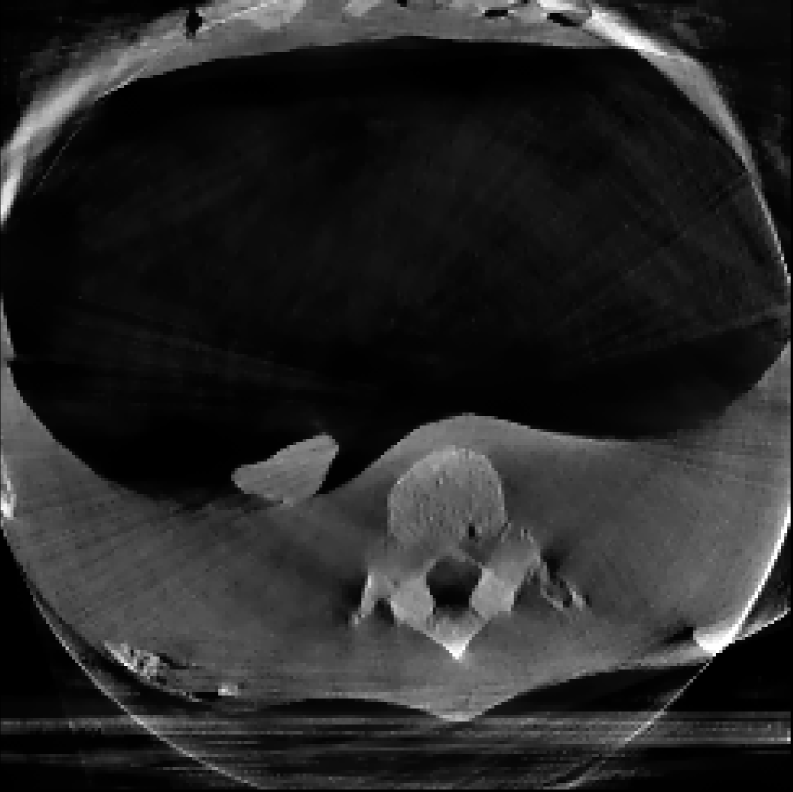

The reconstructions corresponding to the real-scan data with different number of projections (180, 50, and 20, respectively), can be observed in Figures 3, 4, and 5. In all three figures (a) is the prior image 𝒙p\boldsymbol{x}_{p} used for prior image regularization, (f) is the ground truth image; and the rest of images correspond to different reconstructions (top) with their corresponding errors (bottom). Analogously to the previous experiment, the difference images (or error) should be completely black in the case of a perfect reconstruction and high intensity indicates more inaccurate reconstructions.

Note that the real data contains a lot of measurement noise, and due to the presence of the needle, the reconstructions can suffer from strong metal artifacts. Therefore, the reconstructed images using different algorithms, particularly without explicit regularization, tend to show strong errors even with a high number of projections. Accordingly, all the algorithms with explicit regularization perform better in this scenario, and particularly those including PIPLE or PICCS regularization. Moreover, the proposed IRN-PIPLE algorithm significantly outperforms other methods, and IRN-PICCS is not far behind. Using only TV regularization struggles to separate artifacts from features, oversmoothing images and thus loosing important image features. Notably, the proposed methods reconstruct high quality images in less than 2 minutes in an implementation that is not optimized to solve this specific geometry.

Figure 3: Reconstructed images using real measurements of a thorax phantom with 180 projection. The reconstructed images are shown in [0, 0.03]; difference images in [–0.04, 0.04].